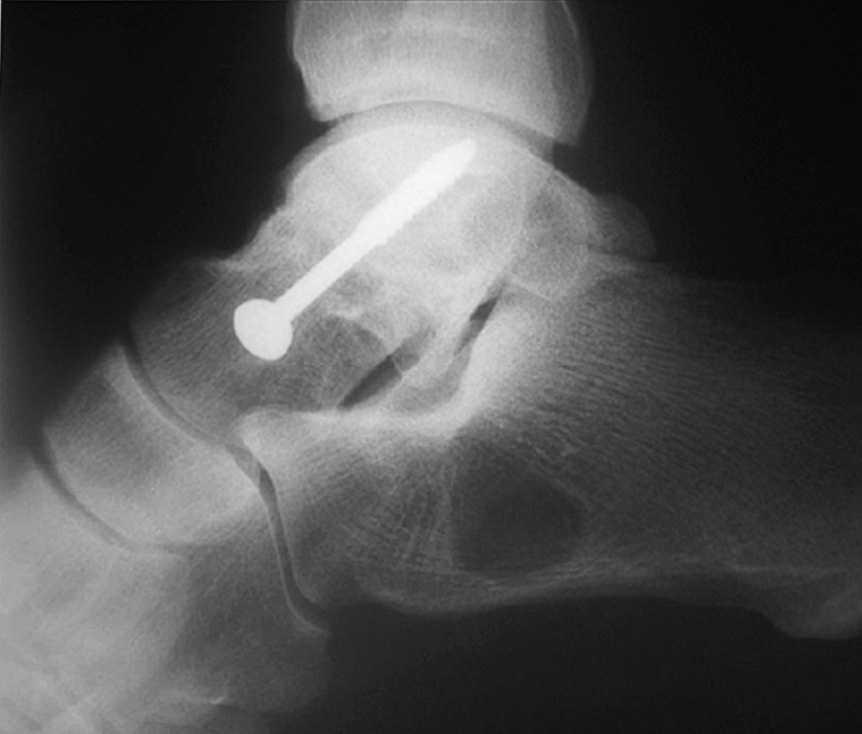

Hemos realizado tan sólo 1 caso debido a una pseudoartrosis (figs. 11 y 12), que se complicó posteriormente con una osteomielitis aguda por lo que se le realizó los 3 tiempos de Papineau. En líneas generales, la talectomía no ha demostrado buenos resultados.

Fig. 12. --Pseudoartrosis y NAV en fractura de cuello de astrágalo. Artrodesis tipo Blair

Fig. 12. --Pseudoarthrosis and avascular necrosis in a fracture of the astragalus neck. Blair-type arthrodesis.